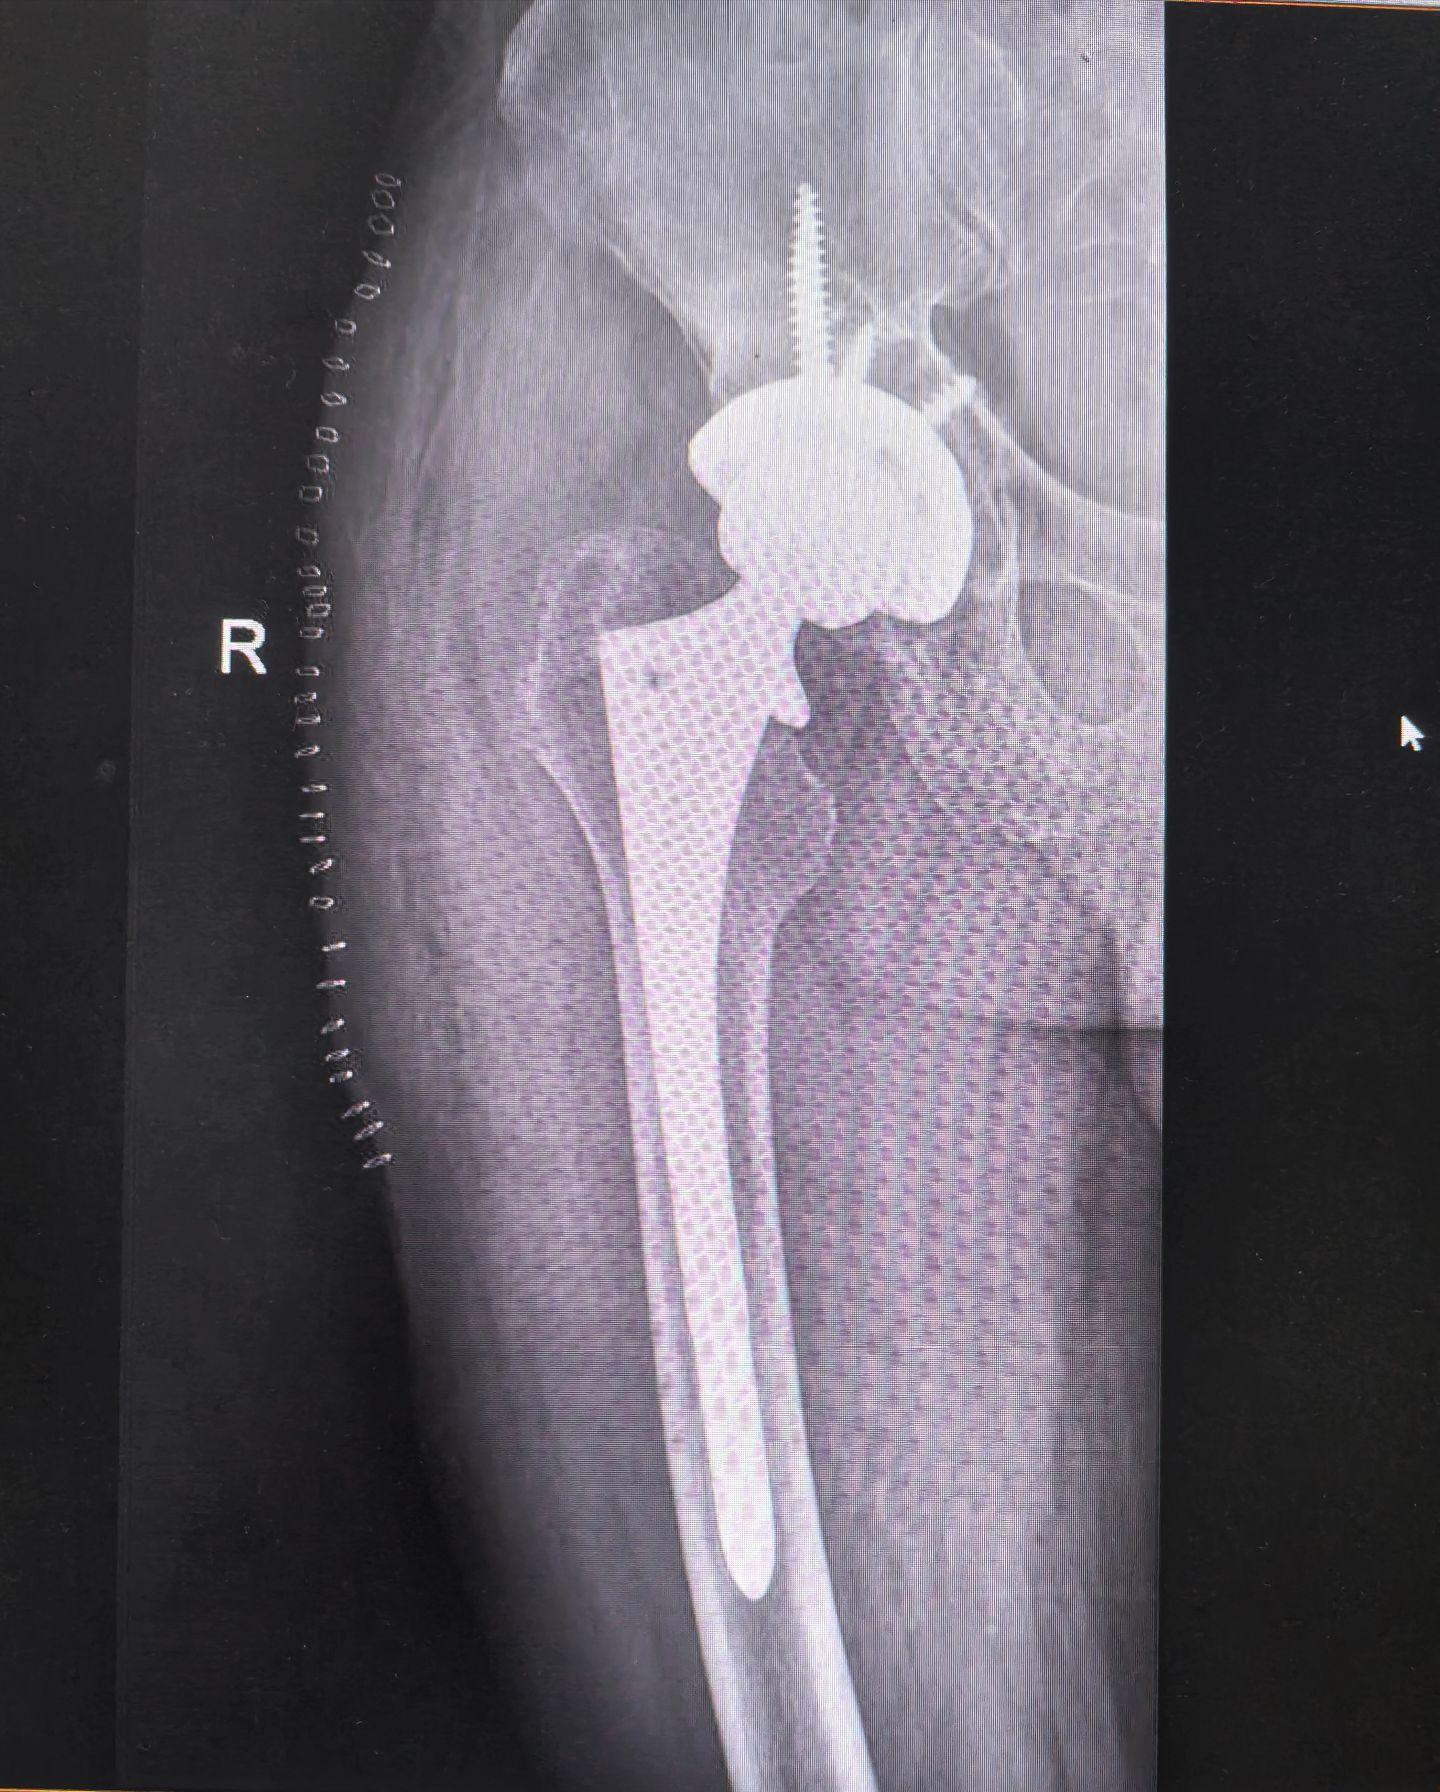

髋关节置换术后假体松动。髋关节置换术后假体松动,一定要做髋关节ct,此例髋臼内壁缺损明显,好在髋臼环完整,缺损处植骨,髋臼初始稳定性良好,术后两天正常下床,患者满意度很高🌹